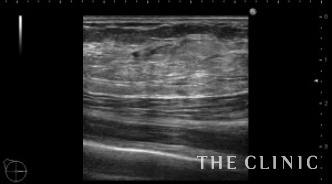

ほとんどの壊死脂肪が除去できました。

吸引した壊死脂肪です。